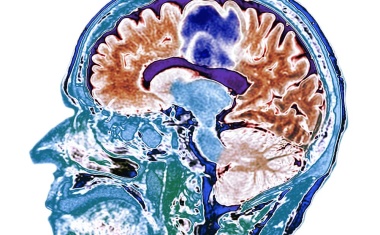

Das ungenutzte Potenzial digitaler Technologien bei Schizophrenie

Vom Smartphone zur Diagnose – Forscher*innen zeigen in einer systematischen Übersichtsarbeit, wie Smartphones und Wearables die Diagnostik und Vorhersage von Schizophrenie-Spektrum-Störungen revolutionieren könnten .